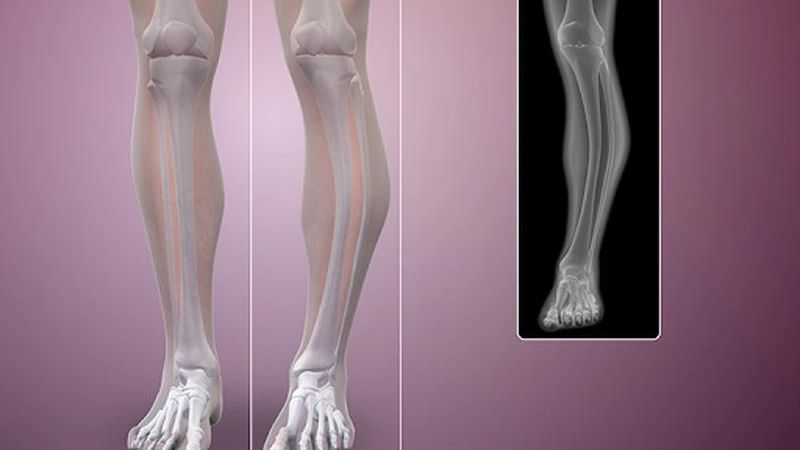

U xương ác tính là một trong những căn bệnh nguy hiểm nhất ở xương. Chẩn đoán u xương bằng sinh thiết xương dưới cắt lớp vi tính giúp ngăn chặn sớm tình trạng này.

Khối u xương ác tính là tình trạng phát triển bất thường trong tế bào xương. Khối u không chỉ ảnh hưởng đến chức năng vận động mà còn khiến người bệnh tàn phế suốt đời. Việc chẩn đoán sớm bệnh nhờ kỹ thuật sinh thiết xương dưới cắt lớp vi tính giúp ngăn chặn những biến chứng xấu xảy ra. Hãy cùng Nhà thuốc Long Châu tìm hiểu về kỹ thuật sinh thiết trong bài viết dưới đây.

Quá trình sinh thiết xương dưới cắt lớp vi tính là một phương pháp y tế, trong đó một kim được đưa qua da và trực tiếp vào xương để thu thập một mẫu nhỏ từ cơ thể. Mẫu này sau đó được kiểm tra dưới kính hiển vi để phát hiện các bệnh lý như ung thư, nhiễm trùng và các tình trạng khác. Kết quả của quá trình này cung cấp thông tin quan trọng để giúp bác sĩ đưa ra quyết định về phương pháp điều trị cho bệnh nhân.